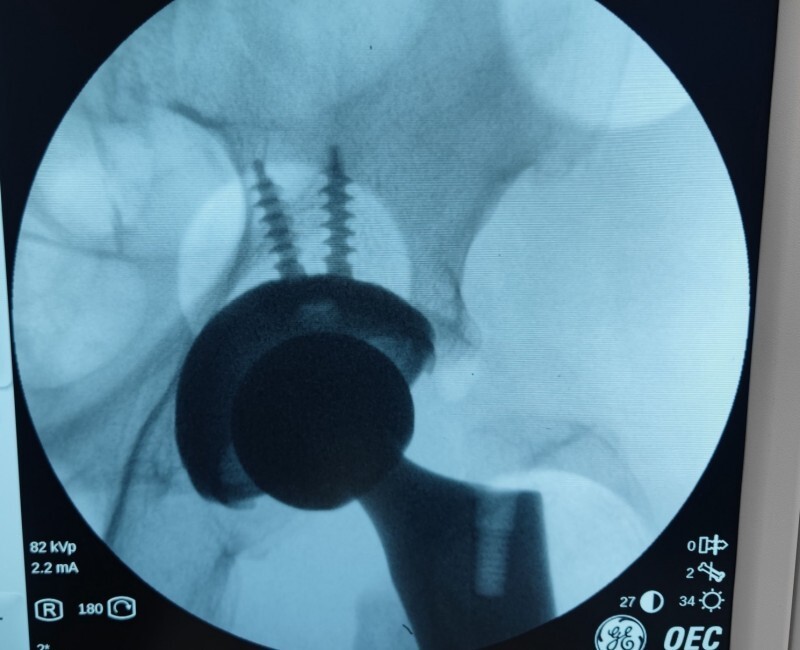

第2例:机器人辅助下全髋关节置换术

歙县人江某某,81岁,一周前在家中不慎摔倒后疼痛不已,被家人送来黄山新晨医院就诊,经过仔细检查后确认为“左股骨颈骨折”入院。

考虑到患者年龄较大,且基础疾病较多,骨科团队经过周密考虑讨论之后,建议其家属考虑机器人手术,在仔细了解手术机器人的相关知识后,其家属欣然接受,并表示江老先生很幸运,赶上了好机会。手术历经两个小时左右顺利结束,目前江老先生各项情况良好。